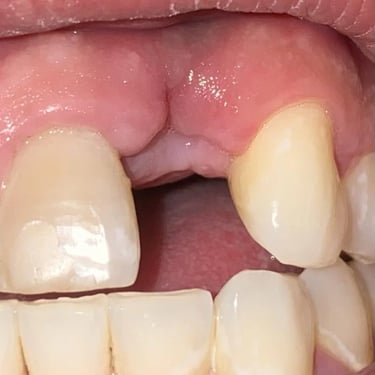

Pérdida de múltiples dientes

La pérdida de múltiples dientes es la ausencia de varios dientes que puede ser resultado de caries, enfermedades periodontales o traumatismos.

Los pacientes notan varios espacios vacíos en su boca, lo que afecta su capacidad para masticar y hablar adecuadamente.

El tratamiento incluye la colocación de varios implantes dentales para restaurar la función y la estética.